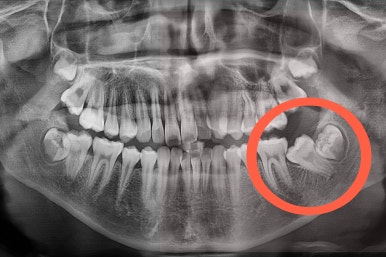

X-ray를 보면 사랑니가 어부바 하고 있어서 나와야 될 어금니가 짓눌려 있는 양상이었어요.

이 경우 방향을 잘못잡아서 바로 앞 어금니도 밀어버리거나 해를 가할 수 있는 상황이었습니다.

사랑니가 잘못 나는 바람에 사랑니 포함 치아 3개가 문제될 수 있는 상황이었어요.